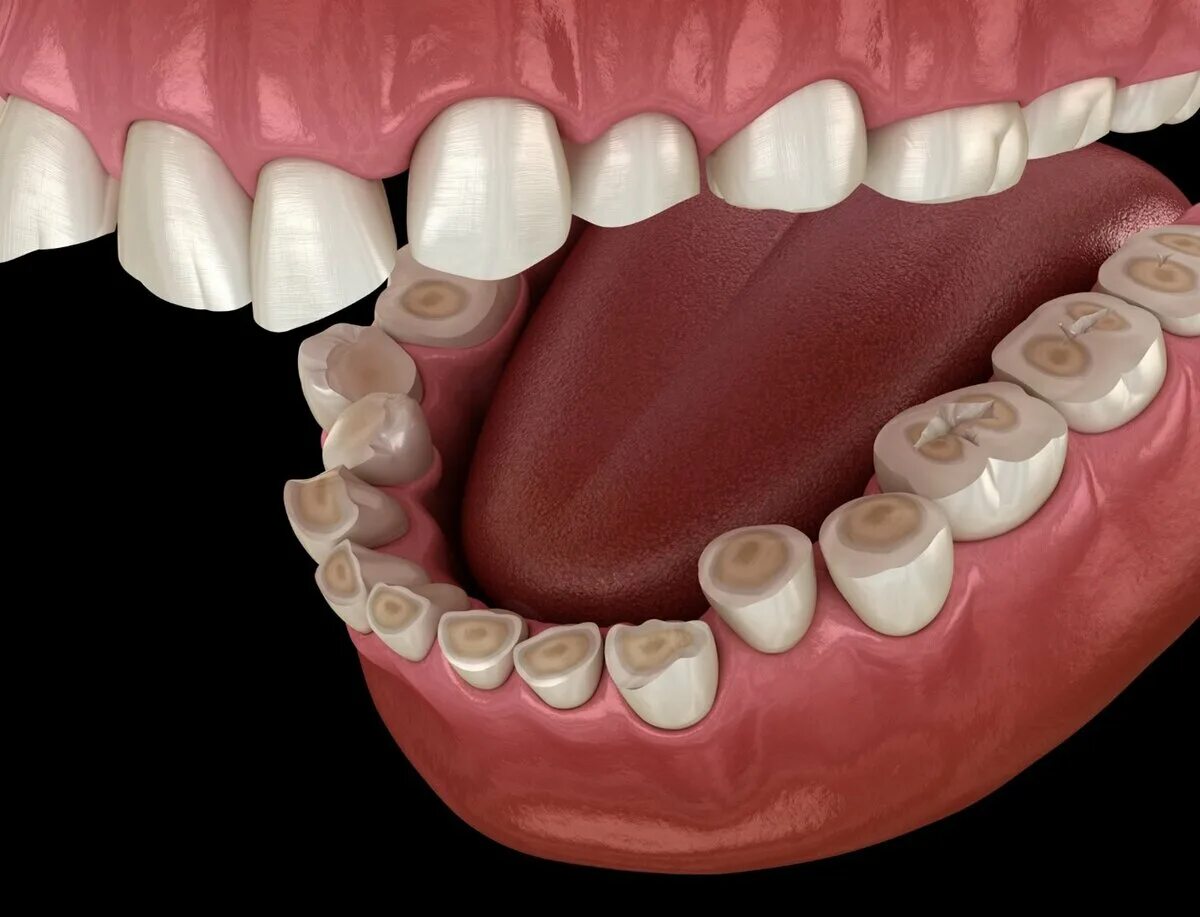

Зубы зажаты